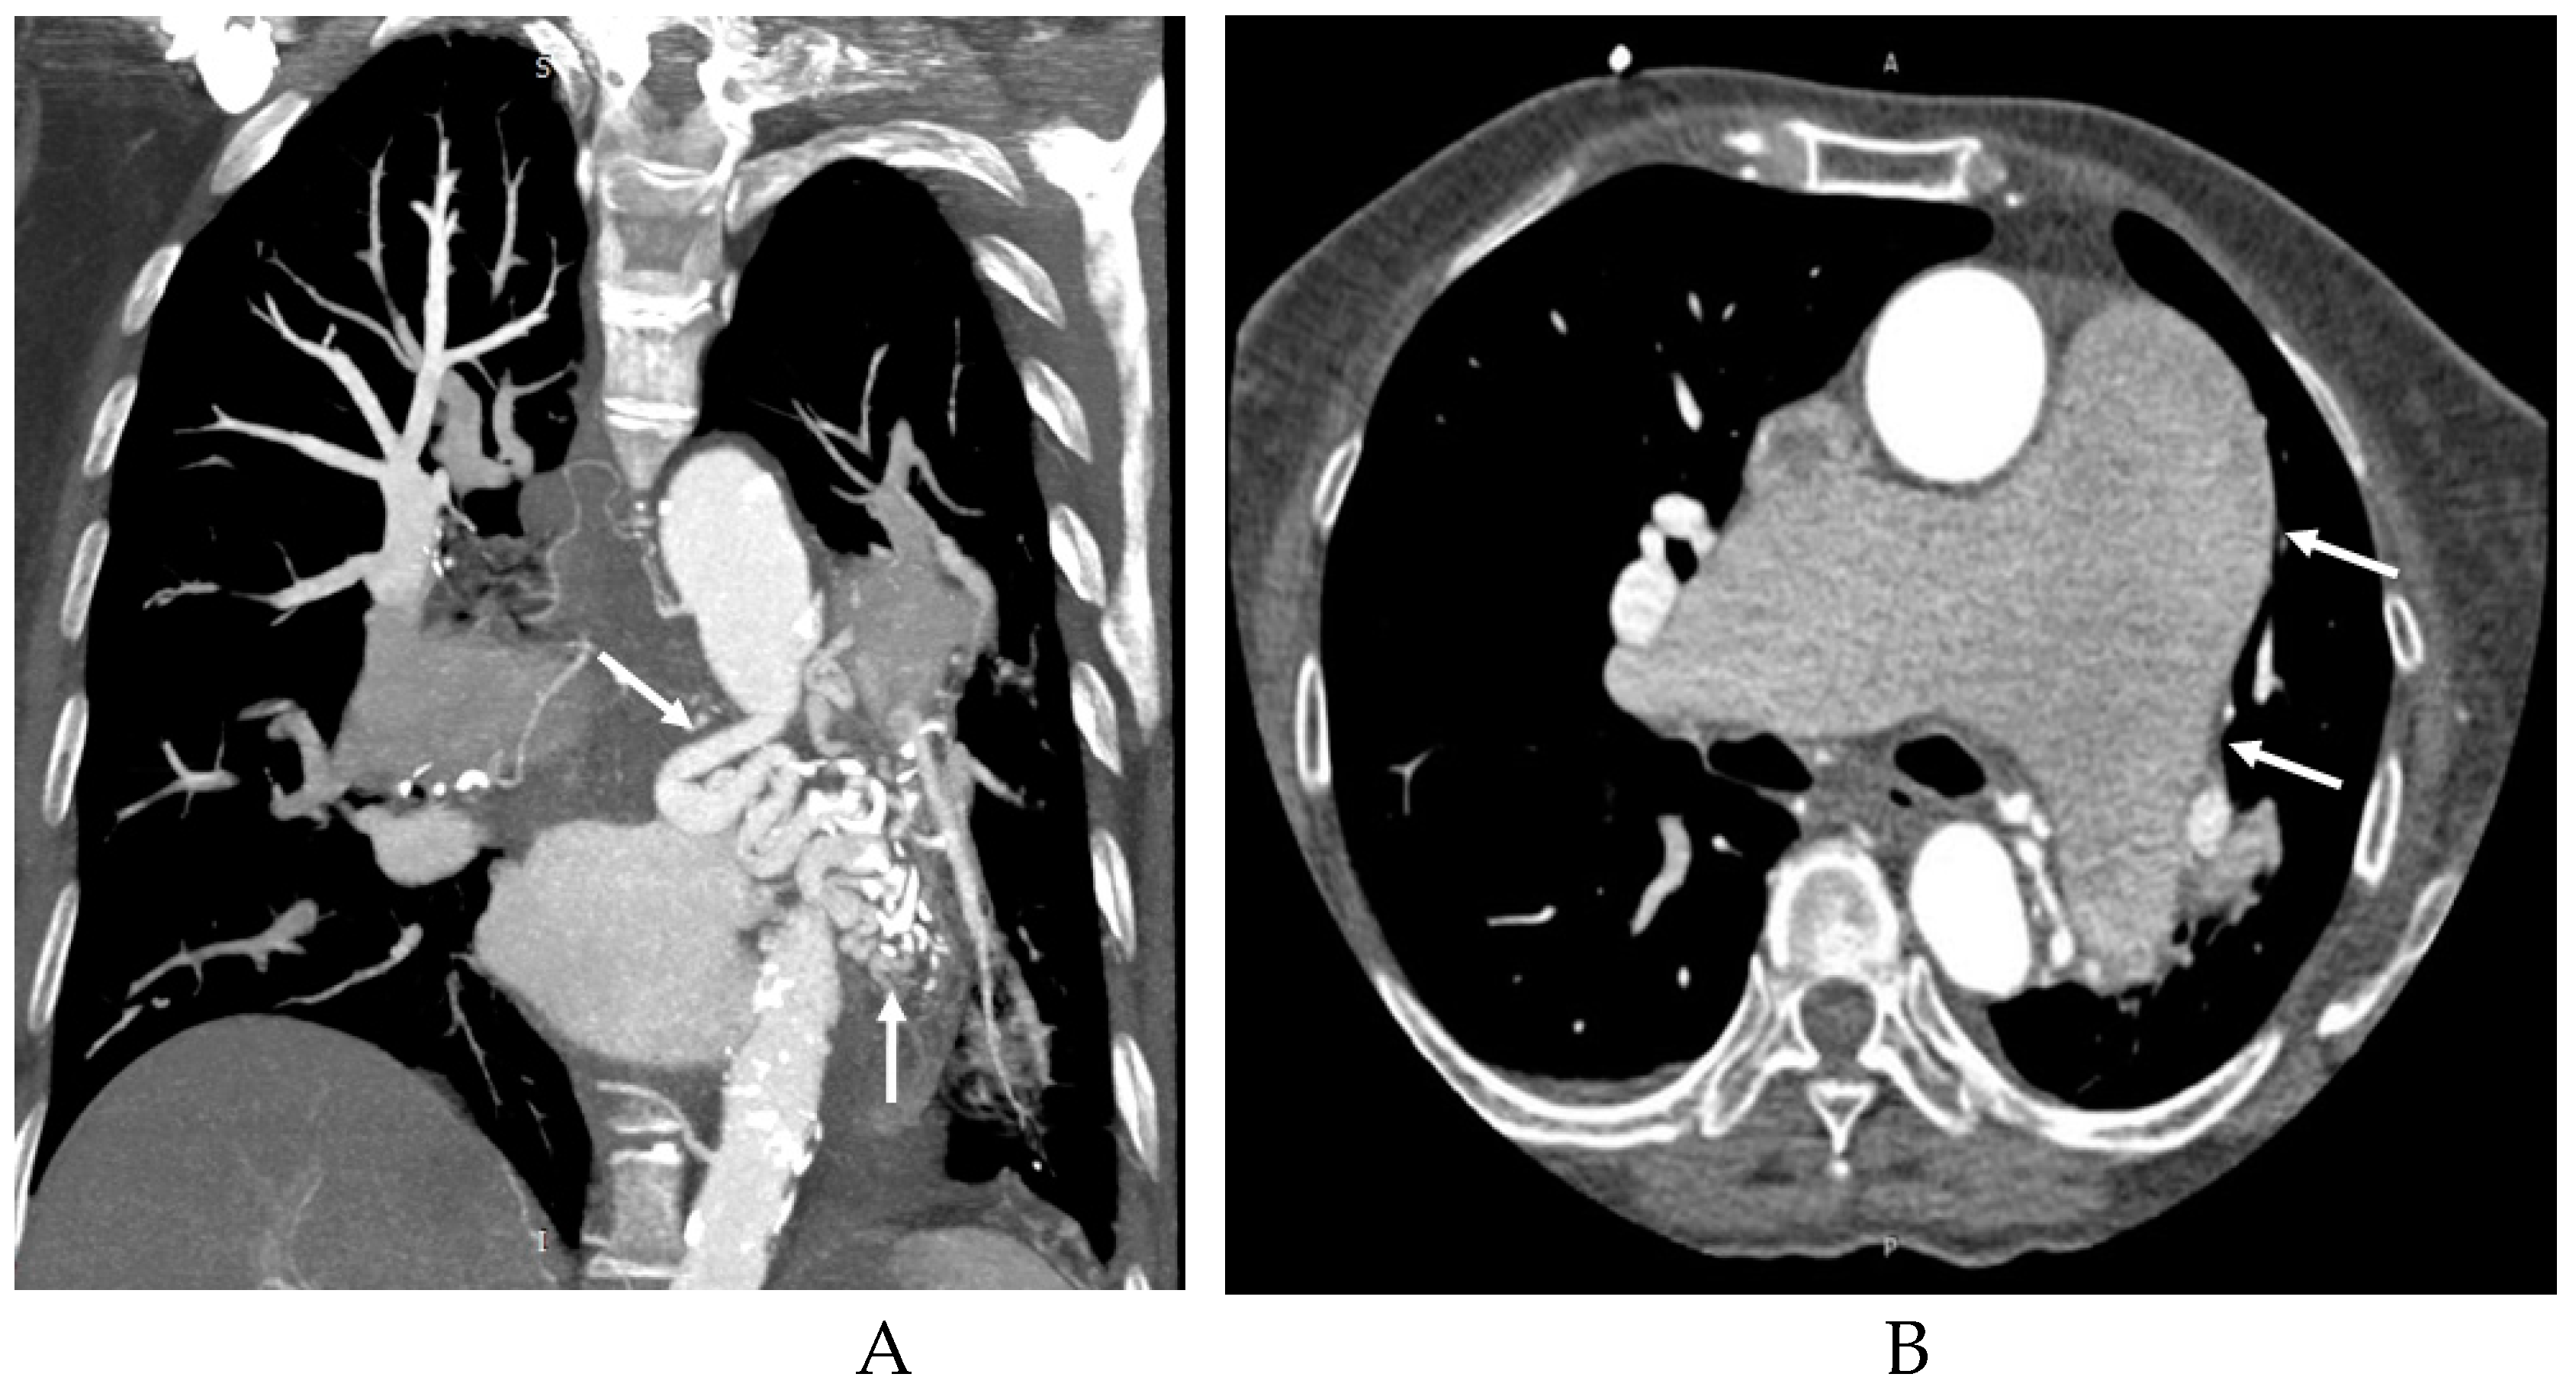

3.2. Imaging appearances of CTPA

| Draining vessels | PV | 49(89.09%) |

| UV | 1(1.82%) | |

| IV | 1(1.82%) | |

| PA | 11(20.00%) | |

| NF | 2(3.64%) |